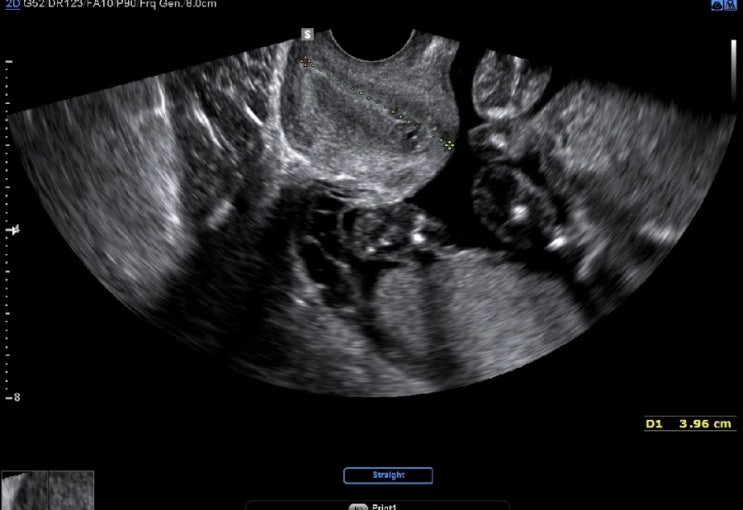

임신 23주 5일 초음파, 경부길이

2023.08.17. 세브란스 다녀온 지 벌써 2주! 지난번에도 경부길이가 조금 짧게 나왔기 때문에, 경부길이랑 ...